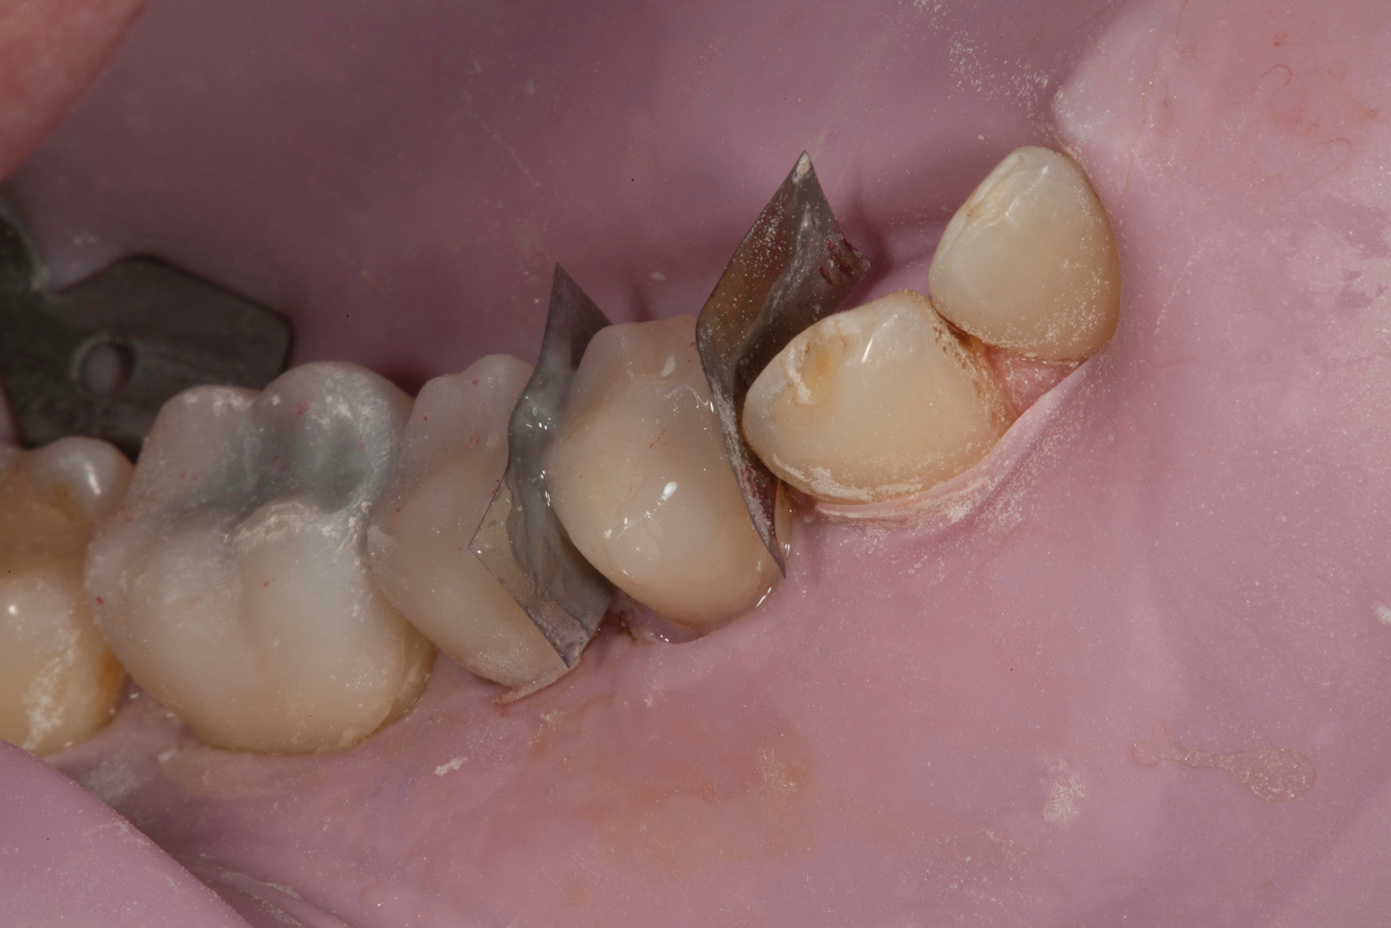

Fig 6. Fitting of prefabricated posterior units.

Figure 6